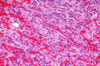

8. You perform a biopsy of a palatal lesion in an HIV+ individual. A representative microscopic image is shown below. Which of the following is true regarding this lesion? a. It is best diagnosed as Kaposi Sarcoma b. It is caused by HHV-8 c. It may also be seen in patients who are status-post organ transplant d. All of the above are true

d. All of the above are true